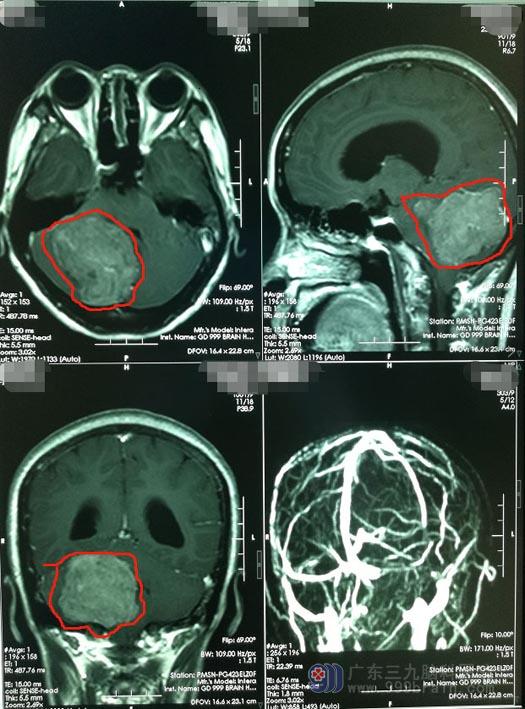

近半年来,刘阿姨出现了右侧面部麻木并逐渐加重,当地医院的头颅CT提示“右侧小脑占位并梗阻性脑积水”,头颅MR显示“右侧后颅窝占位并梗阻性脑积水,考虑脑膜瘤”。入住广东三九脑科医院神经外五科,进一步头颅MRI示:“右侧跨小脑幕上下巨大占位,考虑脑膜瘤,梗阻性脑积水”。

小脑幕脑膜瘤是指肿瘤基底附着在小脑幕,易向幕上及幕下两个方向生长,小脑幕巨大跨幕脑膜瘤是指瘤基底附着于小脑幕或小脑幕切迹处,瘤体横跨小脑幕、瘤径≥3cm的颅底肿瘤,由于该位置毗邻重要的血管神经结构,全切肿瘤一直是神经外科的手术难点。

患者病史长,且肿瘤巨大已经跨小脑幕上下生长,头颅血管造影检查提示肿瘤血供丰富,肿瘤还侵犯了颅内重要的静脉窦,所以更增加了手术的难度,术中出血会比较多,术后也可能出现严重的并发症。肿瘤大部位于后颅窝,瘤体已巨大,若不及时进行手术,会出现慢性枕骨大孔疝的急性发作,导致生命危险。